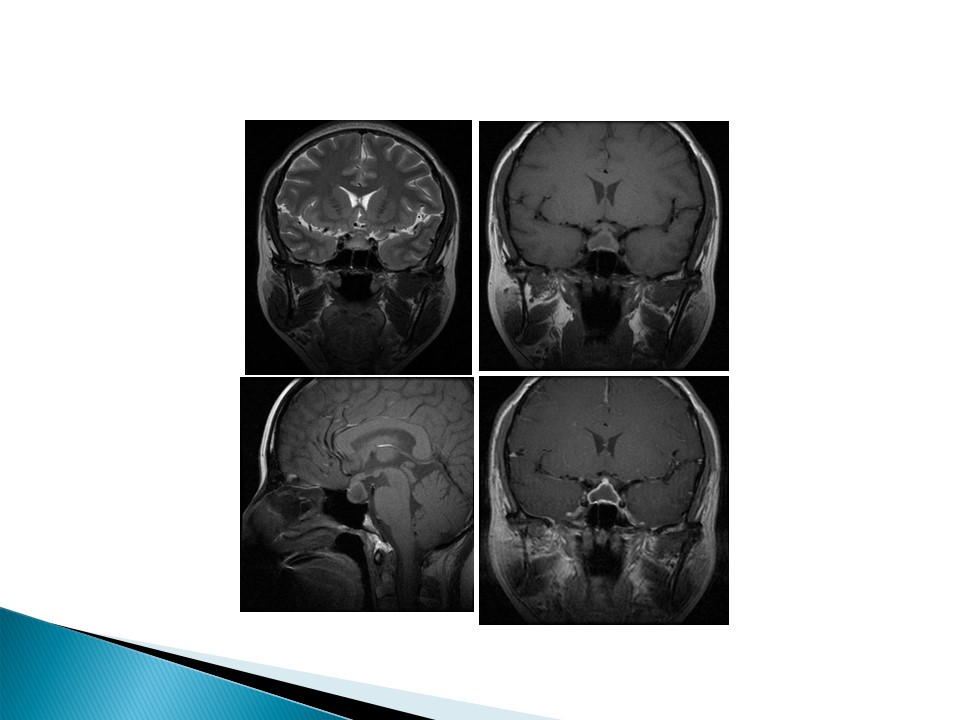

“垂体疾病的影像诊断” 的相关文章